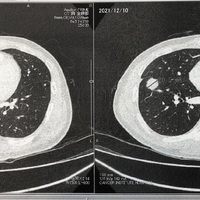

【治験スチバーガ終了】12月24日CT結果

最近、ブログを書くのが少し後回しになってしまいます。ダメですね。 しっかりタイムリーに書くようにしないと! さて、昨年末、12月24日のクリスマスにCTの結果を聞きにいきました。 結論から言うと、昨年8月から治験を初めて、約8mmくらい大きくなっていました。 この治験は5mm以上大きくなってしまうと終了しないといけ…